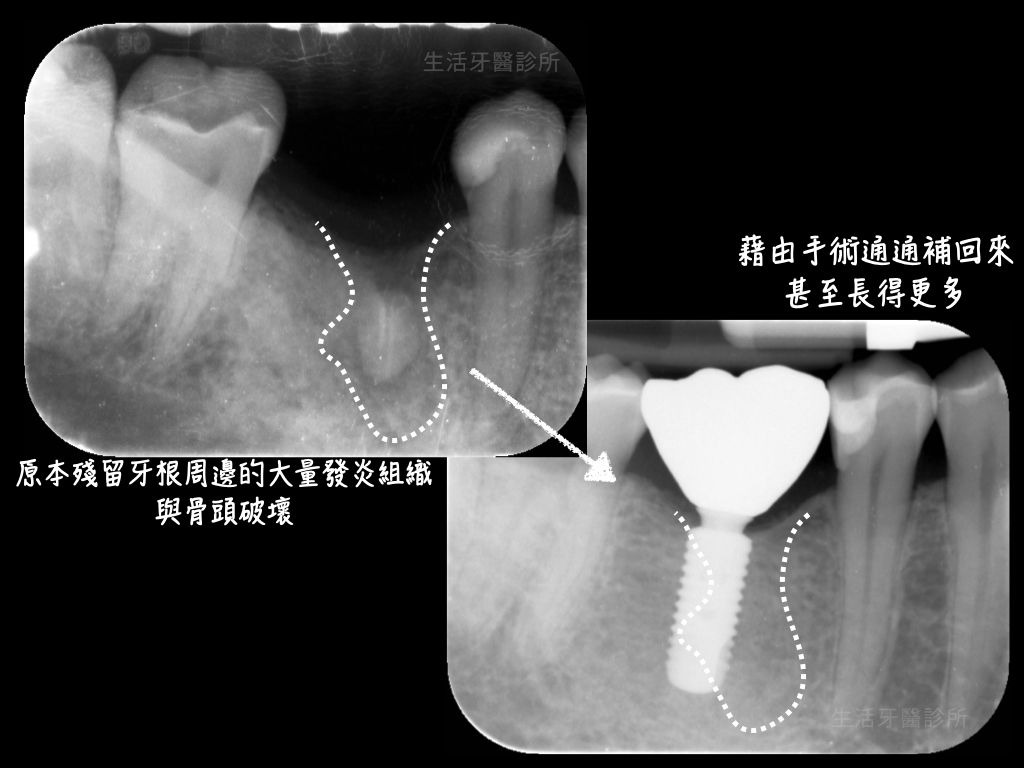

陳先生多年前在其他家診所拔除右下第一大臼齒,空著很久,終於下定決心要來植牙。從X光片可以看到,竟有牙根沒被拔乾淨。與陳先生討論後,由於殘留牙根周邊有大量的發炎組織與骨頭破壞,建議先進行翻瓣手術,將沒拔乾淨的牙根清除,並同時進行「齒槽骨保存術」,待骨頭癒合良好之後再進行植牙的治療。

由圖示比較,可以明顯看出,原本殘留牙根周邊的大量發炎組織與骨頭破壞,通通藉由手術補回來。甚至在適當的假牙製作下,長得更多!